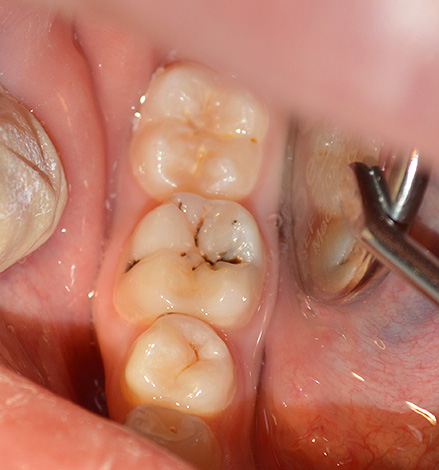

Na fase de cárie secundária, via de regra, é observada uma destruição bastante rápida da dentina, cuja estrutura porosa é preenchida com muitas bactérias cariadas. No entanto, a forma mais grave e negligenciada de cárie é a forma profunda, quando uma cavidade profunda e cárie se forma no contexto da rápida destruição da estrutura da dentina. Ao mesmo tempo, apenas alguns milímetros (muitas vezes até frações de milímetro) permanecem na polpa, e o fundo da cavidade é coberto com tecidos dentários amolecidos, pigmentados e deteriorados. A cárie profunda nominal é a mais perigosa em termos de transição para uma doença mais grave - a pulpite.

É assim que uma cárie profunda se parece: